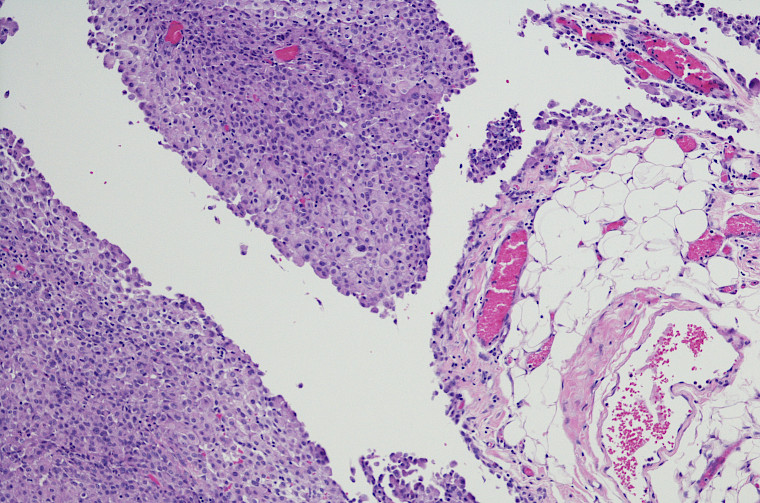

Au cours des 5 dernières années, plusieurs groupes européens ou nord-américains ayant une expertise démontrée dans le traitement du mésothéliome pleural ont rapporté des chiffres de mortalité chirurgicale bien inférieurs à ceux de MARS2 et des survies à long terme meilleures sur des cohortes de plus de 100 patients. Ce mois-ci, nous avons publié dans Annals of Surgery notre expérience de 152 patients traités par traitement trimodal à Londres entre 2004 et 2019. Les patients avaient tous eu une pleurectomie / décortication, 96% avaient reçu une chimiothérapie préopératoire ou adjuvante et tous à l’exception de deux avaient reçu une radiothérapie prophylactique sur leur paroi thoracique un mois après l’intervention. Nous n’avons eu aucune mortalité chirurgicale à 90 jours et la survie médiane de nos patients était de 31,7 mois. Les patients porteurs d’un mésothéliome épithélioide (70%) avaient une médiane de survie de 35 mois, tandis que ceux porteurs d’un mésothéliome biphasique ou sarcomatoїde avaient une survie médiane de 18,3  mois. Fait important : nous avons préservé le diaphragme chez 87,5% de nos patients, alors que le diaphragme était réséqué et remplacé par une prothèse synthétique chez plus de 80% des patients dans MARS2 et EORTC-L1205.

Au vu de toutes ces études, nous pensons que la sélection des patients, en particulier en utilisant en routine des biomarqueurs moléculaires et génomiques, l’imagerie avancée par TEP et scanner ou IRM thoracique, est fondamentale pour éviter des chirurgies lourdes et futiles. Les interventions chirurgicales devraient être réalisées uniquement par des chirurgiens thoraciques expérimentés dans des centres experts ayant un volume significatif et disposant d’unités de soins intensifs performantes, car les complications chirurgicales sont fréquentes et parfois graves. Les traitements systémiques par immunothérapie permettent d’obtenir des survies équivalentes au traitement multimodal chez les patients porteurs de mésothéliomes non-épithéliaux, et il semble donc logique de ne pas recommander de chirurgie de cytoréduction chez ces patients. Les patients porteurs de mésothéliomes épithélioïdes dont la tumeur semble extirpable en totalité devraient être adressés à un centre expert pour discussion en tumor board et évaluation.